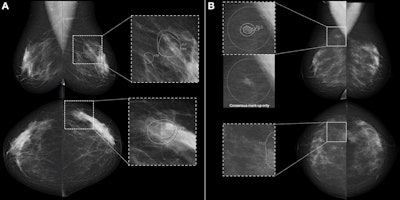

Full-field digital screening mammograms in participants recalled by the consensus discussion after being flagged by artificial intelligence (AI) computer-aided detection (CAD) but not by either of the two radiologists. (A) Mammogram with AI CAD score of 73 for a 55-year-old woman diagnosed with grade 3 in situ cancer and T1 (9-mm) invasive cancer in the left breast and lymph node metastasis. (B) Mammogram with AI CAD score of 54 for a 49-year-old woman diagnosed with grade 2 in situ cancer and T1 (6-mm) invasive cancer in the right breast and without lymph node metastasis. All images and caption courtesy of the RSNA.Full-field digital screening mammograms in participants recalled by the consensus discussion after being flagged by artificial intelligence (AI) computer-aided detection (CAD) but not by either of the two radiologists. (A) Mammogram with AI CAD score of 73 for a 55-year-old woman diagnosed with grade 3 in situ cancer and T1 (9-mm) invasive cancer in the left breast and lymph node metastasis. (B) Mammogram with AI CAD score of 54 for a 49-year-old woman diagnosed with grade 2 in situ cancer and T1 (6-mm) invasive cancer in the right breast and without lymph node metastasis. All images and caption courtesy of the RSNA.